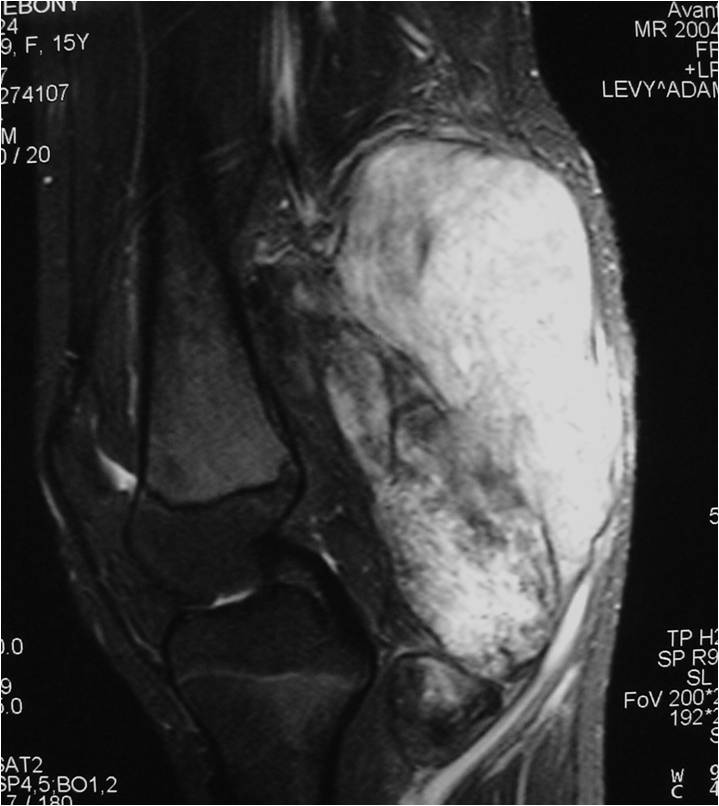

Radiographic Presentation

- Aggressive motheaten to permeative lesion

- Indistinct border in most cases

- Osseous destruction with a soft tissue component

- Chondroid matrix calcification may be present (60-70% of cases)

- Soft tissue mass